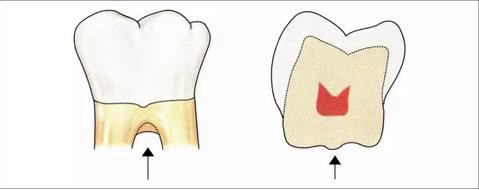

▼圖4 釉突的分類

I度:釉突向根分叉部略微延伸的狀態(tài)。

II度:釉突向根分叉部延伸,沒有到達(dá)的狀態(tài)。

III度:釉突延伸到根分叉部的狀態(tài)。

·釉突的發(fā)生頻率

下頜磨牙:約30%

上頜磨牙:約17%

也就是說在口腔外科,無論是切除療法還是再生療法,都會采取將釉突切除,將根面的牙骨質(zhì)露出,期待在術(shù)后的牙周組織可以擁有健全的附著狀態(tài)的方法。